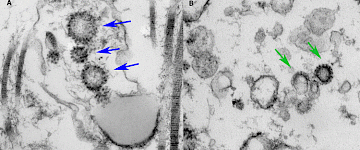

徠卡顯微鏡在鼠耳真皮的熒光免疫

炎癥和重塑過程的活體成像一直是一個重要的研究領域,并還激發(fā)了創(chuàng)造表達的熒光蛋白轉基因無數(shù)記者小鼠模型。我們的論文描述了一種新的體內成像技術,它的設計是基于使用免疫染色對外科手術暴露的小鼠真皮活細胞和組織結構,而不會引起有害的免疫毒性作用的創(chuàng)新概念。在外科手術過程本身是安全的真皮脈管,因為它僅依賴于兩個皮膚層在耳朵被獨立地支配,通過血液中自主供給和由分離淋巴環(huán)流排出分離。